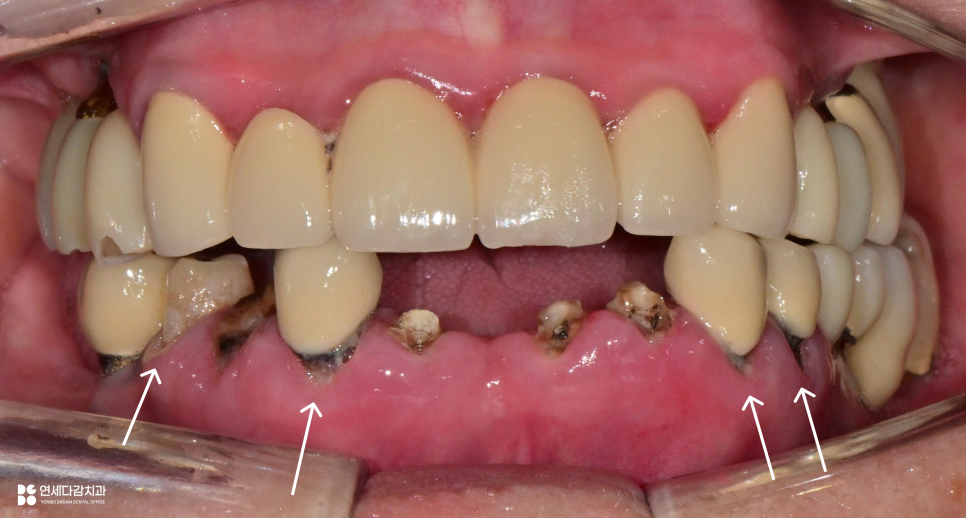

오금역 치과 에서 표시한 것처럼

크라운과 잇몸 사이의 변연 적합도가

저하되어 있는 것으로 평가됩니다.

겉에서는 크라운에 가려진 것 같지만,

실은 치근이 그대로 드러나 있으며

그 사이로 우식이 진행되고 있습니다.

이 또한 우식이 깊어진 상태라면

크라운을 재수복 하더라도

예후가 좋지 않을 가능성이 높습니다.